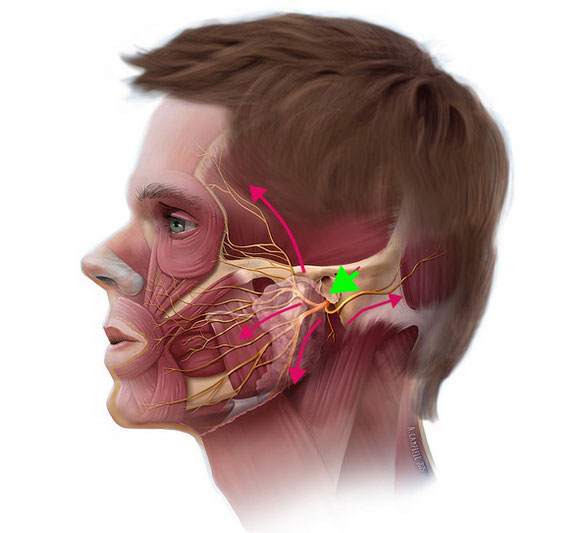

顔面神経の走行 (頭蓋骨の外)

脳から左右1本ずつ顔面神経が出る。

➡頭蓋骨のトンネル中を走行して顔の表面へ向かう。

➡骨のトンネルを抜けて、耳の下から出る。顔面を走行(緑矢印)。

その後に細かく枝分かれをして(赤矢印)、顔面にある幾つかの顔面を動かす筋肉に脳からの指令を伝える。